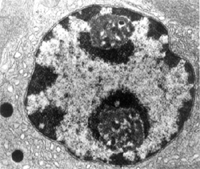

細胞